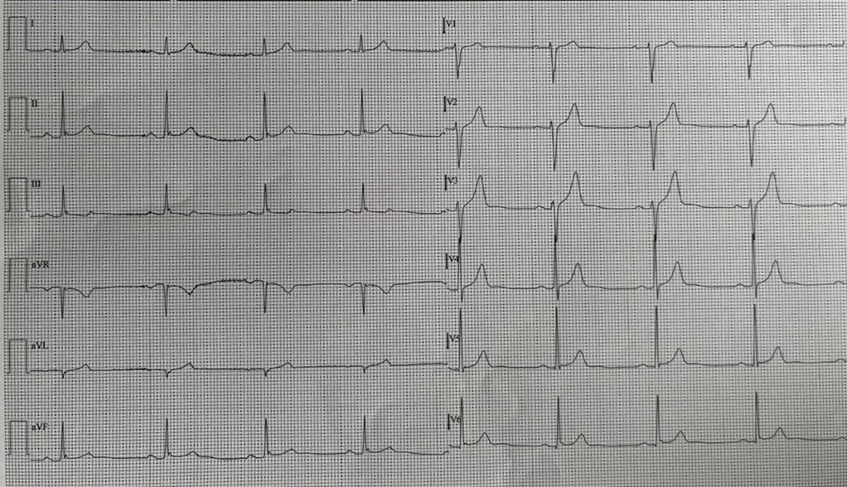

We present the case of a 56-year-old patient, affected by arterial hypertension and with no cardiac history, who called the Emergency number because of an episode of resting angina at home. When emergency vehicles arrive the patient was initially asymptomatic and electrocardiogram was normal. For recurrence of chest pain, a second ECG tracing was performed and it highlighted a second degree atrio-ventricular block, Mobitz 2, ST-segment elevation in the infero-lateral and sub-ST segment in leads V1-V2 (Figure. 1). The patient was then taken to the Hemodynamics of our Hospital for urgent coronary angiography. The exam did not find significant coronary atherosclerosis affecting the epicardial coronary arteries (only a 30-40% stenosis of the right coronary artery in the middle section was described). At the transthoracic echocardiogram performed in the Coronary Unit, significant valvular defects were excluded, the left ventricular ejection fraction (LVEF) was preserved with only a mild hypokinesia of the inferior-posterior wall. In the suspicion of vasospastic angina on the documented atherosclerotic plaque of the right coronary artery, Diltiazem i.v. was introduced into therapy and then orally. In the following 48 hours the patient experienced two different episodes of angina with an ECG tracing compatible with inferior-STEMI and third degree atrioventricular block (Figure. 2). The symptoms rapidly reduced after intravenous nitroglycerin administration, with prompt restoration of sinus rhythm (Figure. 3). Enzyme curve was not significant (hs-TnT 10 ng/L, Ck-Mb 3.4 mcg/L). During the hospitalization the therapy with calcium channel blocker was up-titrated and nitrate was also introduced, without further anginal episodes or major brady-arrhythmias. Considering the mild coronarosclerosis and the high lipoprotein-A levels (Lp(a) 85 mg/dl), we decided to maintain the therapy with acetylsalicylic acid and the Rosuvastatin/Ezetimibe combination. After 5 days the patient was transferred, asymptomatic and with good haemodinamic status, to a cardiac rehabilitation facility. At the follow-up visit in the Day Hospital Ambulatory, 3 months later, the echocardiogram was normal, and the drug therapy was well tolerated. No new arrhythmic events were detected at the control Holter ECG.

Figure. 3: Normalization of the trace and restoration of sinus rhythm after administration of nitrate i.v. during coronary spasm